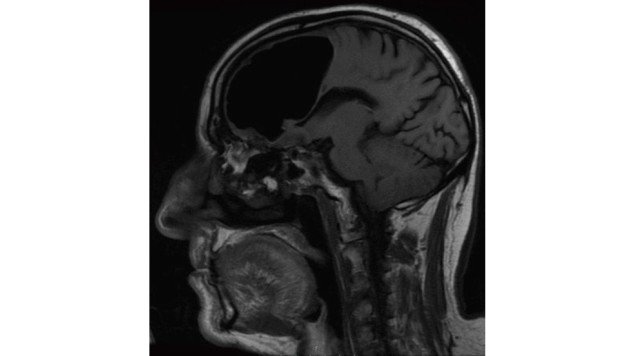

Tras la tomografía y la resonancia magnética se llevaron una gran sorpresa porque todo el lóbulo frontal derecho del sujeto estaba desaparecido. “Todos estábamos perplejos por lo que vimos”, relató Finaly Brown al Washington Post, médico del departamento de emergencias del hospital Causeway en Coleraine (Irlanda del Norte).

Según determinaron que el anciano padecía neumocefalia, presencia de aire en el cráneo, una condición que suele presentarse en casos de cirugía al cerebro, infecciones o heridas faciales, aunque con burbujas o espacios de aire mucho más pequeños, pues en este caso, la cavidad llegaba a medir casi nueve centímetros de largo en su parte más grande.

Según el equipo de médicos, la causa más probable fue un tumor benigno formado en los senos paranasales del paciente, que erosionaron la base del cráneo y permitieron la formación de la cavidad.(Agencias)]